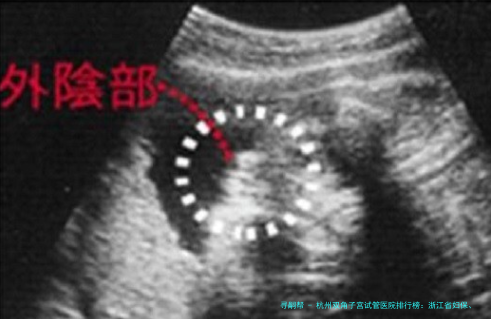

4杭州市妇幼保健院生殖医学中心1953年(医院),生殖中心近年发展迅速杭州市级重点专科,具备开展各项辅助生殖技术的资质。位于医院新院区,环境明亮温馨。服务注重人文关怀,针对高龄、疑难患者有特别关注。配置了高清阴道超声用于精准移植定位,以及胚胎冷冻复苏优质系统。“本地医院,沟通方便。胡晓君主任亲自做B超看我的子宫形态,讨论了很久才确定移植策略,感觉很负责任。”——用户李女士

简介:专注于女性不孕不育症的超声诊断与治疗,尤为擅长使用三维超声等影像技术评价双角子宫等畸形样子,为移植提供准确导航。临床操作技术精湛。